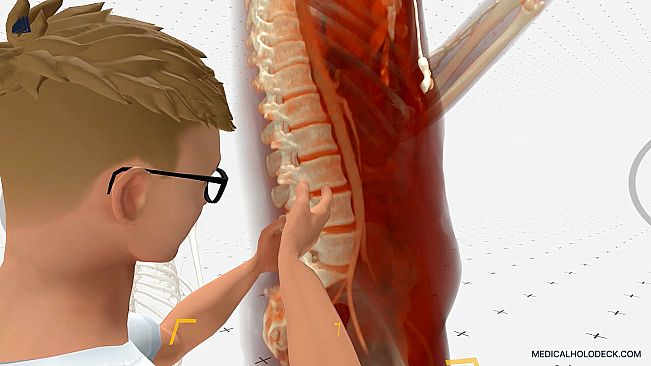

Experience medical education in virtual reality. Explore detailed 3D human dissections and 3D anatomy models. Automatically segment CT scans with AI, and exercise surgeries in an immersive environment.

Developed for future doctors, surgeons, nurses, and medical students, Medicalholodeck provides an immersive 3D environment to interact with patient data, medical imaging, high-res anatomical dissections, and anatomy models.

Explore human anatomy in full 3D, from any angle and scale. Examine pathologies in detail and deepen your medical understanding.

Dissection Master XR – VR-based human anatomy atlas and dissection lab, offering professional human dissections.